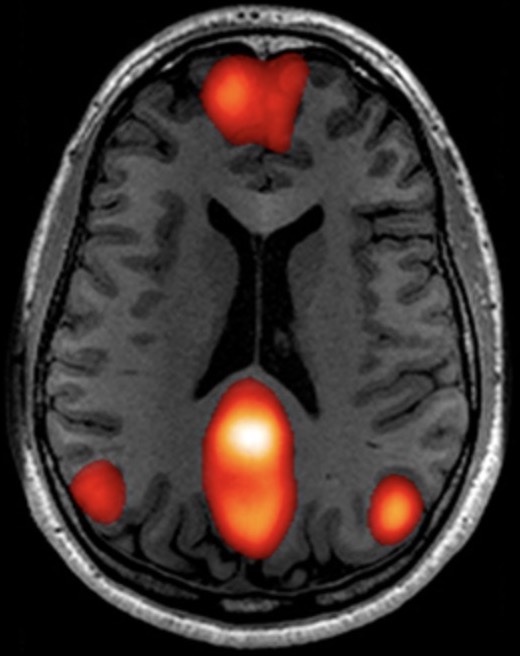

1. fMRI数据预处理;2.常见fMRI指标的原理与计算;3.SPM统计分析与多重比较校正;4.独立成分分析(ICA)与功能网络连接(FNC);5.结果可视化;6.脑结构磁共振成像(sMRI)分析基础:VBM分析;7.脑白质弥散加权成像(DWI)分析基础:TBSS分析等。